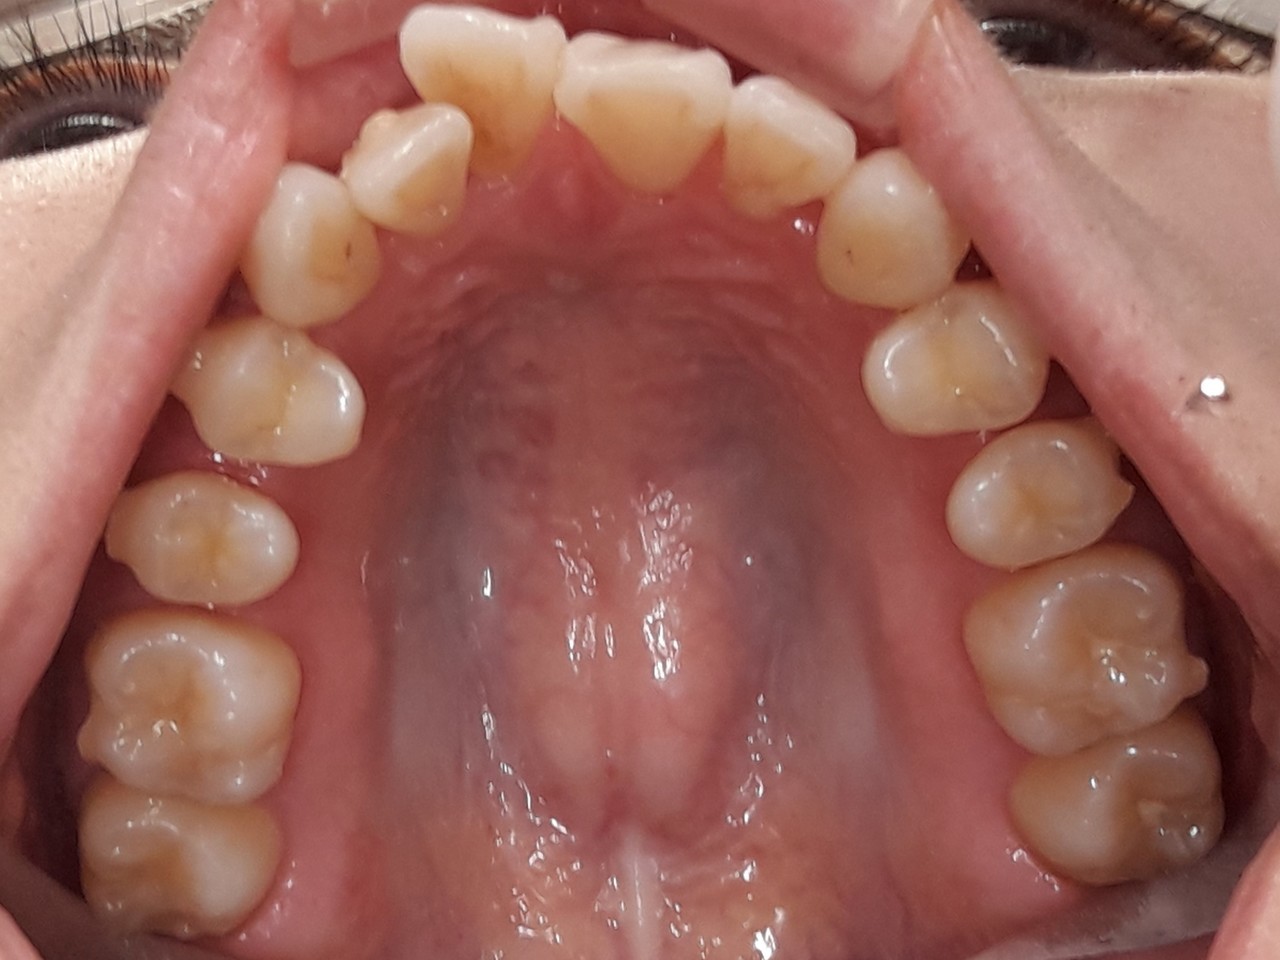

インビザ開始して6ヵ月がたちました。

下顎は綺麗にそろいましたが、上顎はまだまだです

今は噛み合わせが高くなっているため、「いー」の口のときすき間ができています。